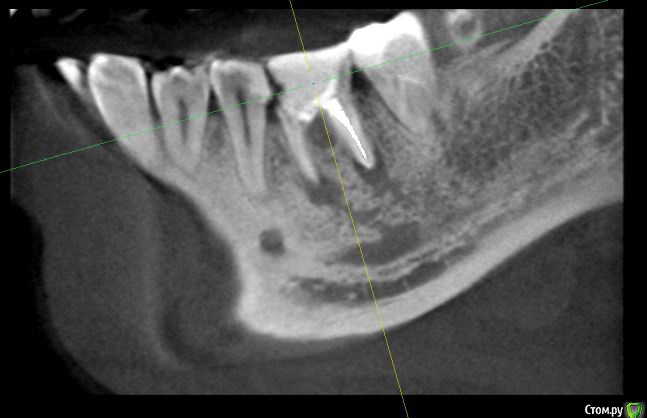

dok1 Опубликовано 8 ноября, 2016 Поделиться Опубликовано 8 ноября, 2016 И присмотритесь к следующему зубу. Ссылка на комментарий

dok1 Опубликовано 8 ноября, 2016 Поделиться Опубликовано 8 ноября, 2016 К семёрке. Следующий двухкорневой. Ссылка на комментарий

anvladd Опубликовано 8 ноября, 2016 Поделиться Опубликовано 8 ноября, 2016 Кариес под пломбой Ссылка на комментарий

IvanK Опубликовано 9 ноября, 2016 Поделиться Опубликовано 9 ноября, 2016 +1, удалять убрать нависающий край пломбы на 5ке Ссылка на комментарий